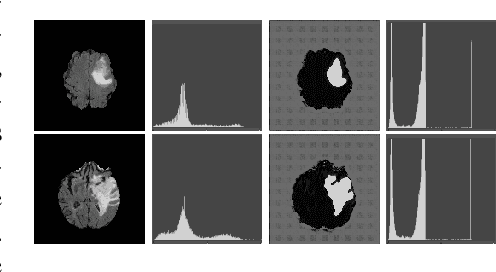

We introduce a neural network framework, utilizing adversarial learning to partition an image into two cuts, with one cut falling into a reference distribution provided by the user. This concept tackles the task of unsupervised anomaly segmentation, which has attracted increasing attention in recent years due to their broad applications in tasks with unlabelled data. This Adversarial-based Selective Cutting network (ASC-Net) bridges the two domains of cluster-based deep learning methods and adversarial-based anomaly/novelty detection algorithms. We evaluate this unsupervised learning model on BraTS brain tumor segmentation, LiTS liver lesion segmentation, and MS-SEG2015 segmentation tasks. Compared to existing methods like the AnoGAN family, our model demonstrates tremendous performance gains in unsupervised anomaly segmentation tasks. Although there is still room to further improve performance compared to supervised learning algorithms, the promising experimental results shed light on building an unsupervised learning algorithm using user-defined knowledge.